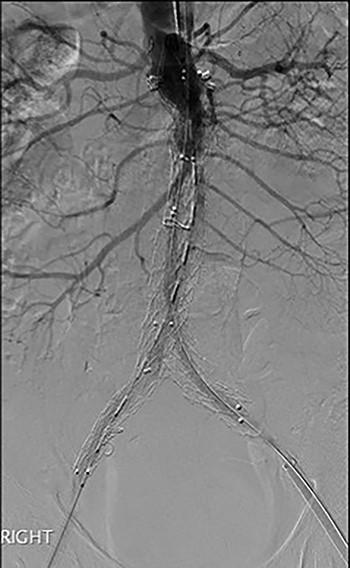

Post-EVAR angiogram showing acute thrombosis of the right limb and subtotal thrombosis of the left limb and trunk.

An angiogram at this stage demonstrated acute thrombosis of the right limb, and subtotal thrombosis of the left limb (Fig. 2). A further bolus of 2000 units Heparin was given intravenously. Thrombectomy was performed by advancing the 16Fr Sentrant sheaths into the limbs of the endograft followed by retraction under negative pressure. This manoeuvre restored antegrade arterial flow on both sides although there was a large volume of acute thrombus within the limbs of the endograft. A decision was made to perform intra-arterial thrombolysis. The 16Fr Sentrant sheath was removed from the left common femoral artery and haemostasis secured with the Proglides. The right-sided 16Fr sheath was downsized to 8 Fr sheath (the Proglide sutures were tightened around this sheath, achieving haemostasis around the smaller sheath). A multi-side hole straight angiographic catheter was placed in the body of the endograft for the thrombolysis. A bolus of 5 mg Actilyse (Boehringer Ingelheim, Ingelheim am Rhein, Germany) was given through this followed by a 1 mg/h infusion. An IV heparin infusion was started at 1000 units/h through the side arm of the 8 Fr sheath.